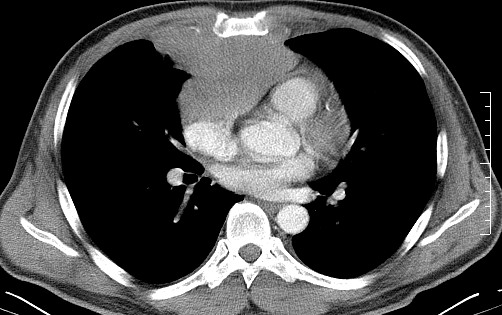

男   40   反复腹痛入院行彩超检查示胸骨右缘4、5肋间不均质回声团

淋巴瘤:前纵隔可见多组肿大的淋巴结,部分融合,有液化坏死

上区却那么有点象占位,胸腺瘤不太象,一点强化也没有,淋巴瘤气管前上腔静后却很干净,下区也点象纵隔积血征,

莲蓬籽征  考虑淋巴瘤

结果是淋巴瘤呀,谢谢了!